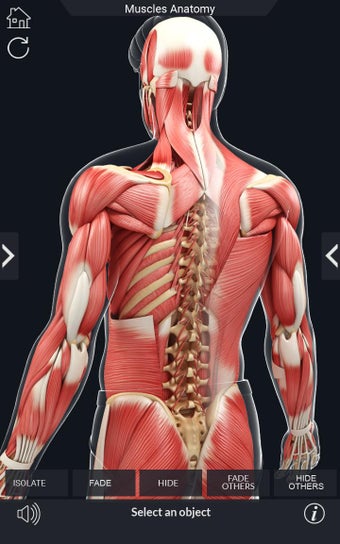

Den mest omfattande mobilappen som finns i världen för att studera muskelanatomi, som låter dig rotera 360°, zooma och flytta kameran runt en mycket realistisk 3D-modell.

Det finns många verktyg tillgängliga för varje muskel, inklusive:

- Rotera 360°.

- Zooma in och ut.

- Flytta kameran runt modellen.